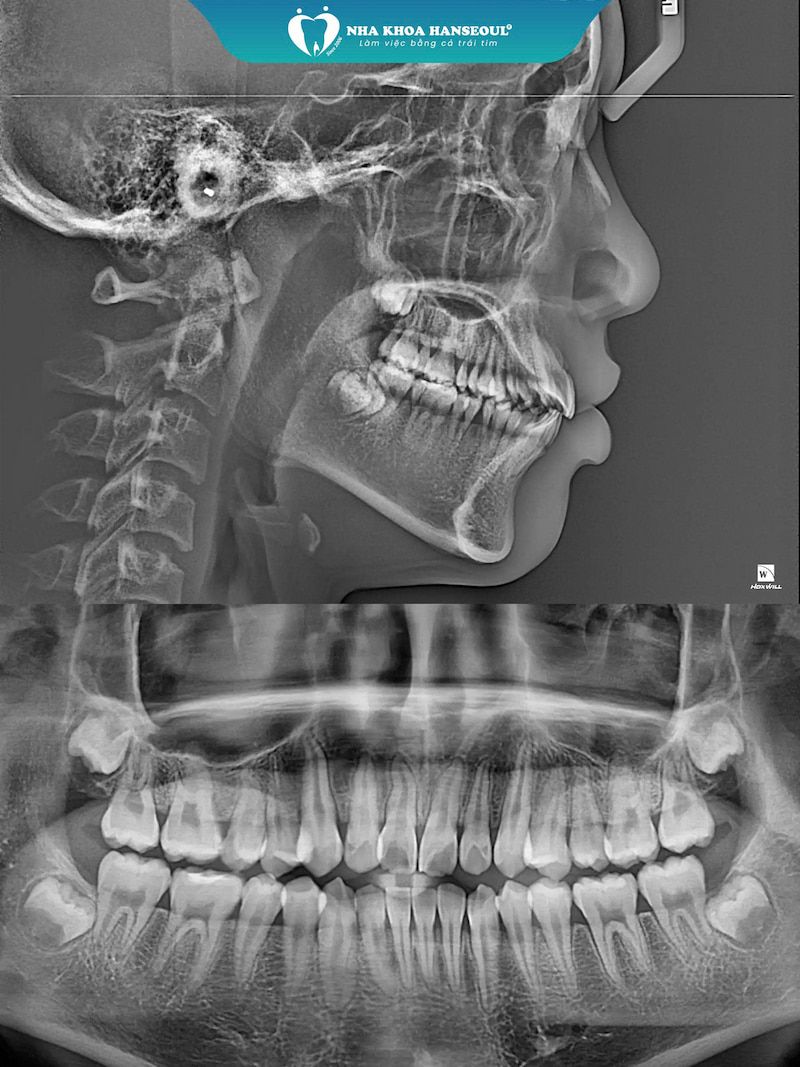

Ngày 20/10/2024 đánh dấu khởi đầu hành trình thay đổi nụ cười của Khánh Việt. Sau khi thăm khám, chụp phim và tư vấn chi tiết với bác sĩ Huyền – chuyên gia chỉnh nha tại Hanseoul, chị Huỳnh Hoa đã chọn phương pháp niềng Invisalign cho con mình, để con tự tin hơn khi đến trường. So với niềng răng mắc cài, niềng trong suốt giúp răng dịch chuyển hiệu quả, vẫn đảm bảo thẩm mỹ trong quá trình điều trị.

Với công nghệ niềng răng hiện đại, độc quyền - Biosmart tại Hanseoul, bác sĩ Huyền lập kế hoạch dịch chuyển răng chi tiết, mô phỏng nụ cười sau niềng để Việt có thể thấy rõ lộ trình và kết quả.

Sự khác biệt tại Hanseoul đến từ tay nghề bác sĩ, công nghệ hiện đại và quy trình chăm sóc chuẩn quốc tế. Toàn bộ quá trình thực hiện trong phòng chỉnh nha vô khuẩn một chiều, sử dụng hệ thống Máy Scan Trios 3Shape (Đan Mạch) và máy CT Conebeam, cùng phần mềm ClinCheck 3D, giúp bác sĩ lập kế hoạch dịch chuyển răng chính xác tới từng micromet.

Đặc biệt, Hanseoul áp dụng công nghệ BIOSMART – giải pháp chỉnh nha thông minh kết hợp 3Shape, WebCeph và Biotech, giúp lên kế hoạch điều trị chuẩn xác, dự đoán nụ cười sau niềng và đảm bảo quá trình dịch chuyển răng nhẹ nhàng, sinh học, rút ngắn thời gian nhưng vẫn đạt thẩm mỹ tối ưu. Đội ngũ bác sĩ giàu kinh nghiệm, theo sát từng giai đoạn, đảm bảo kết quả ổn định và nụ cười hài hòa với khuôn mặt.